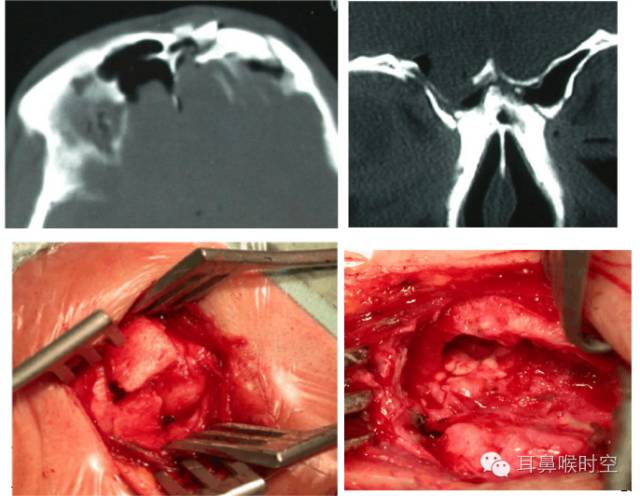

漏口处理

制备移植床:在漏口周边的黏膜、骨质以及脑膜缘搔刮形成2~3mm新鲜创面,如有脑膜脑膨出,可作电凝切除。

给移植物提供一个黏附的区域有利于新骨形成和骨炎性骨的形成。

如果在移植物和移植床之间使用骨移植物,那么就使环绕在缺损周围的骨质增厚,有助于骨性闭合。

漏孔封闭方法

外贴法:漏口<2mm采用筋膜外贴法

夹层法:(2mm~5mm)筋膜-肌肉-筋膜

>5mm:筋膜-支撑材料-肌肉-筋膜

浴缸塞法

修补漏孔的方式

硬材料修补较大颅骨缺损

鼻中隔黏膜瓣修补

浴缸塞法(压塞式)